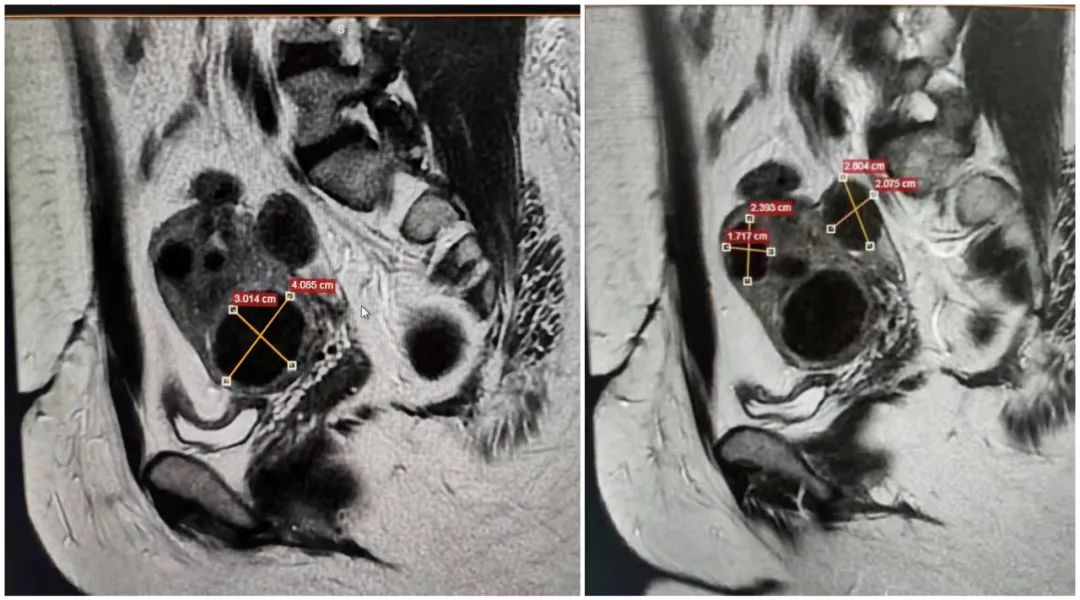

患者42岁,痛经多年,盆腔磁共振检查提示多发性子宫肌瘤合并子宫腺肌病,由于该患者体型特别肥胖、腹部脂肪厚,加上曾经有过腹部手术史,为聚焦超声消融手术增加了极大的难度。

经过59分钟的精心治疗,肌瘤和腺肌病灶都得到成功消融,术中术后没有任何不适,术后休息片便回家了,患者惊呼: "It's amazing!"